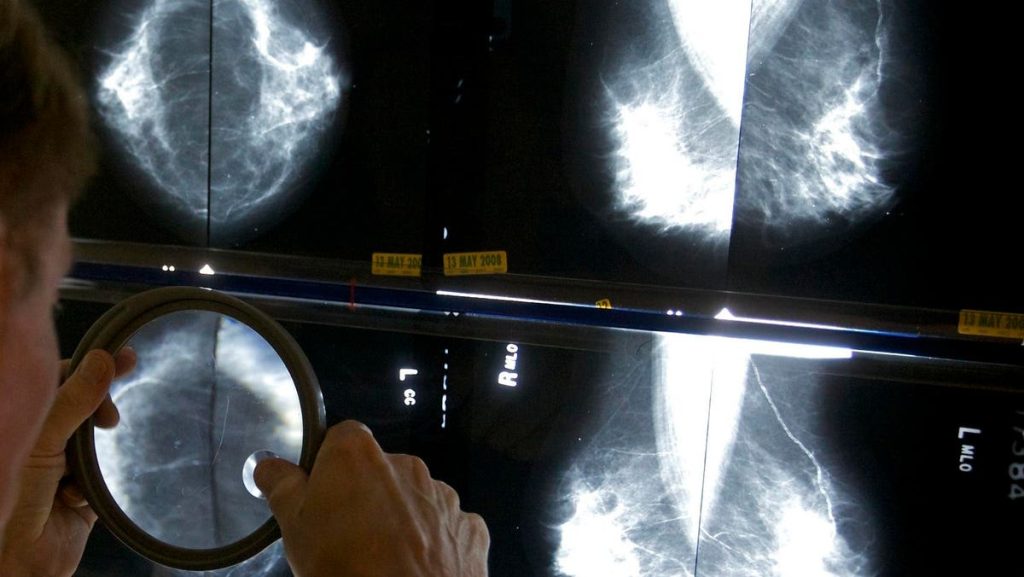

Can artificial intelligence (AI) help detect breast cancer? A new study out of Sweden has tentatively said: yes.

The study enrolled over 80,000 women in a clinical trial to ask this question. All 80,033 underwent mammography. Half of those mammograms were interpreted the standard way in Sweden, which is by two physicians. The other half had their mammograms read by a physician (or two physicians) who had an AI-supported analysis.

What’s an “AI-supported analysis?” That’s when the AI system reviewed the images of the mammogram first, then gave the images a score from 0-10. The image and the score then was reviewed by a radiologist (or two radiologists if the score was 10, the highest risk score).

The study found that AI-supported screening found 20% more cancers as compared to the standard review by physicians who did not use AI.